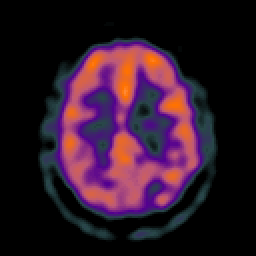

Glioma overlay -- Slice #20

[Home][Help][Clinical] Slice 20